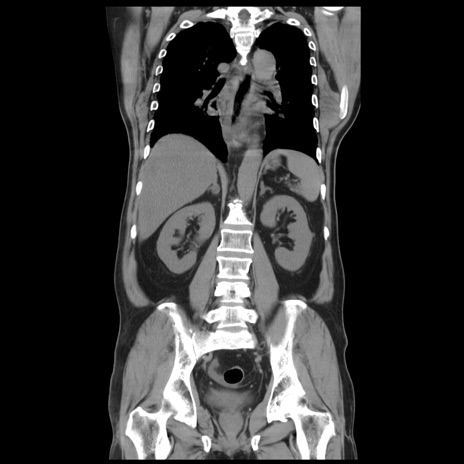

症例20(冠状断像)